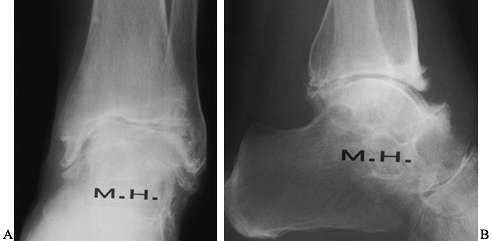

involvement of the ankle joint (Fig. 117.4). Wagner (94)

![]() |

Figure 117.4. Anteroposterior (AP) (A) and lateral (B) radiographs demonstrating ankle arthritis and spontaneous subtalar fusion in a patient with longstanding rheumatoid arthritis.